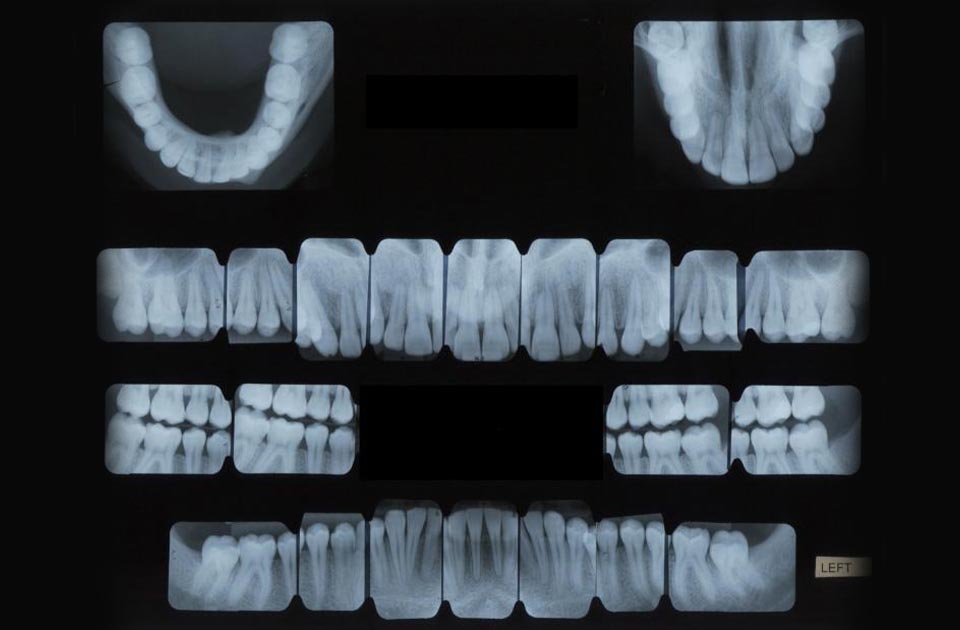

گاهش اوقات دندانپزشک ما برای اینکه تشخیص دقیق تری داشته باشد نیازمند عکس هایی توسط اشعه ایکس می باشد تا بتواند روی کار خودش تمرکز لازم را داشته باشد و کار خود را به درستی انجام دهد .

تصویربرداری از دهان و دندان یکی از مهم ترین اقداماتی می باشد که باید انجام بدهید و در تشخیص دندانپزشک مورد نظر شما بسیار موثر می باشد معمولا بسیاری از کلینیک های دندانپزشکی از این تکنولوژی بهره مند هستند و کمتر کلینیک های دندانپزشکی می باشند که نیازمند به این تکنولوژی هستند .

اشعه ایکس دندانپزشکی مزایای زیادی را دارد و به ارائه دهندگان خدمات دندانپزشکی این مزایای مهم را نشان می دهد اشعه ایکس به دندانپزشکان کمک می کند تا : وضعیت دندان ها ، ریشه ها ، محل قرارگیری فک و ترکیب استخوان صورت شما را به صورت دقیق تر ببیند .

اشعه ایکس می تواند باعث شود که مشکلات دندانی در مراحل اولیه خود پیدا شوند و قابل درمان باشند تا به مشکلات جدی تری بر نخورید .

با کمک اشعه ایکس دندانپزشکان می توانند مشکلات دهان و دندان بیمار ها را مشاهده کنند و از مشکلات آن ها با خبر بشوند اشعه ایکس می تواند مشکلات دندانی زیر را تشخیص دهد :

پوسیدگی دندان ها مخصوصا در نواحی که پوسیدگی دندان کوچک است و در بین دندان ها قرار دارد و دیدن آن با چشم ساده نیست .

پوسیدگی در زیر دندان های پر کرده

از دست رفتن استخوان فک

تغییرات در کانال ریشه یا استخوان به علت وجود عفونت زیاد

آبسه دندان

دیدن دندان نهفته و ..

انواع رادیوگرافی دندان

رادیوگرافی خارج دهان

رادیوگرافی داخل دهان

انواع رادیوگرافی داخل دهان

1 رادیو کرافی بایت وینگ

2 رادیوگرافی پری اپیکال

3 رادیوگرافی اکلوزال

انواع رادیوگرافی خارج دهان

1 رادیوگرافی پارانومیک از کل دهان

2 توموگرام

3 رادیوگرافی سفالومتریک

4 سی تی اسکن با اشعه مخروطی